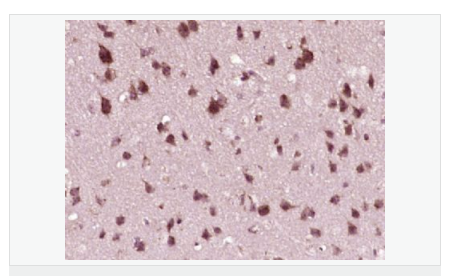

產(chǎn)品介紹This gene encodes a member of the interferon regulatory transcription factor (IRF) family. The encoded protein is found in an inactive cytoplasmic form that upon serine/threonine phosphorylation forms a complex with CREBBP. This complex translocates to the nucleus and activates the transcription of interferons alpha and beta, as well as other interferon-induced genes. Alternatively spliced transcript variants encoding multiple isoforms have been observed for this gene. [provided by RefSeq, Nov 2011].

Key transcriptional regulator of type I interferon (IFN)-dependent immune responses and plays a critical role in the innate immune response against DNA and RNA viruses. Regulates the transcription of type I IFN genes (IFN-alpha and IFN-beta) and IFN-stimulated genes (ISG) by binding to an interferon-stimulated response element (ISRE) in their promoters. Acts as a more potent activator of the IFN-beta (IFNB) gene than the IFN-alpha (IFNA) gene and plays a critical role in both the early and late phases of the IFNA/B gene induction. Found in an inactive form in the cytoplasm of uninfected cells and following viral infection, double-stranded RNA (dsRNA), or toll-like receptor (TLR) signaling, becomes phosphorylated by IKBKE and TBK1 kinases. This induces a conformational change, leading to its dimerization and nuclear localization and association with CREB binding protein (CREBBP) to form dsRNA-activated factor 1 (DRAF1), a complex which activates the transcription of the type I IFN and ISG genes. Can activate distinct gene expression programs in macrophages and can induce significant apoptosis in primary macrophages.

干擾素調(diào)節(jié)因子家族是一大類對干擾素起調(diào)控作用的轉(zhuǎn)錄因子的統(tǒng)稱。 一般認為干擾素調(diào)節(jié)因子(IRF)通過調(diào)節(jié)干擾素的表達而行使其抗病毒、應(yīng)激、免疫調(diào)節(jié)功能。近年來,研究人員發(fā)現(xiàn)IRF在細胞凋亡、細胞周期、細胞分化、腫瘤發(fā)生中也起著重要的調(diào)節(jié)作用。